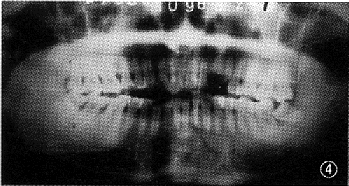

图4 病例1 下颌中线左侧

间斜向后下骨折伴右髁突高位骨折 图5 病例1 小型钛板固定中线左侧斜行骨折,颌间制动10d后,弹力牵引配合张口训练 图6 病例2 左下颌角骨折 图7 病例2 左下颌角骨折,拔除阻生牙,小型钛板固内固定,未行颌间结轧 图8 病例2 术后3个月复查,骨折线已明显愈合改建